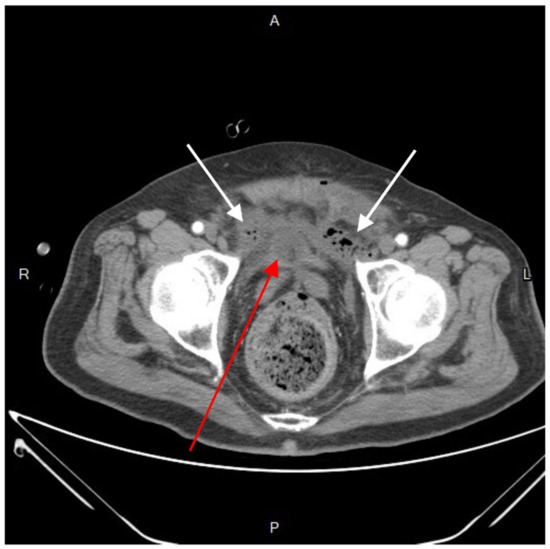

Figure 2. Axial view of contrast-enhanced computed tomography. An emphysematous collection of fluid-and-air-filled cavity (white arrow) in the perivesical space, dominantly on the left side. A Foley catheter with inflated balloon was dwelled in the bladder (red arrow). R, right; L, left; A, anterior; P, posterior.

Further diagnostic measures included a plain abdominal radiograph, which showed no pneumoperitoneum or abnormal fluid accumulation. Laboratory findings consisted of an elevated white blood cell count and C-reactive protein level (white blood cells: 27,830/μL; neutrophils: 90.6%; C-reactive protein: 21.65 mg/L). Abdominal contrast-enhanced computed tomography (CT) showed a heterogenous fluid-filled perianal abscess measuring 5.0 × 4.4 × 6.8 cm (Figure 1) in the left perianal region, with extraperitoneal air spreading through the abdominal wall fascia (Figure 2 and Figure 3). The primary abscess was situated in the supra-levator space, potentially involving the levator muscle (infra-levator), as indicated by its migration from the perianal level to the extraperitoneal level. After a comprehensive review of the patient’s symptoms, medical history, age, and current status, immediate arrangements for endoscopic tests, including upper gastrointestinal endoscopy and colonoscopy, were not made. Additionally, gastrointestinal tract specimens, such as fecal samples for calprotectin and lactoferrin, were not collected, thereby not suggesting the likelihood of inflammatory bowel diseases.

Blood cultures were drawn, and broad-spectrum empiric antibiotics (meropenem) were initiated. Following fluid resuscitation, the patient underwent incision and drainage in the 8 o’clock region. A cystic-like cavity filled with pus and surrounded with granuloma was found. We debrided and irrigated the lesion as much as possible and afterwards placed a Foley tube for adequate drainage and irrigation. Subsequent dressing changes were conducted regularly for proper hygiene. However, ten days after the surgery, the patient experienced sudden massive rectal bleeding, resulting in hypovolemic shock. Upon examination with an anal retractor, an oozing site with active bleeding was identified in the rectum in the 9 o’clock region. On the spot, the bleeding was managed by suturing ligation with 2-0 Vicryl successfully. Meanwhile, a colonoscopy revealed no obvious bleeding, mucosal constriction, fistula, rectal ulcers, or pre-malignant abnormalities. Simultaneously, an emergent abdomen and pelvic CT scan indicated no contrast medium extravasation in the bowel lumen or peritoneal space. Still, it identified an irregularly thick wall at the right side of the rectum (1.85 × 5.9 cm) and an extraperitoneal abscess around the bladder. Despite these findings, an anal-rectal fistula was not observed based on image surveys and physical examinations.